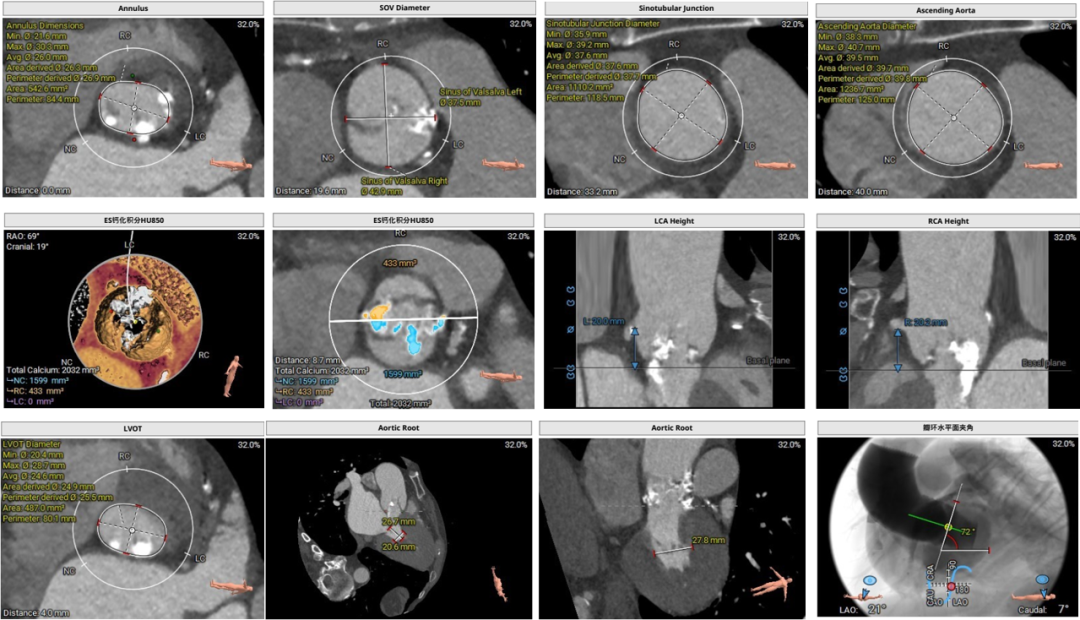

主动脉根部、升主动脉、冠脉及左室评估

应用基于人工智能技术的术前分析辅助决策软件进行术前评估